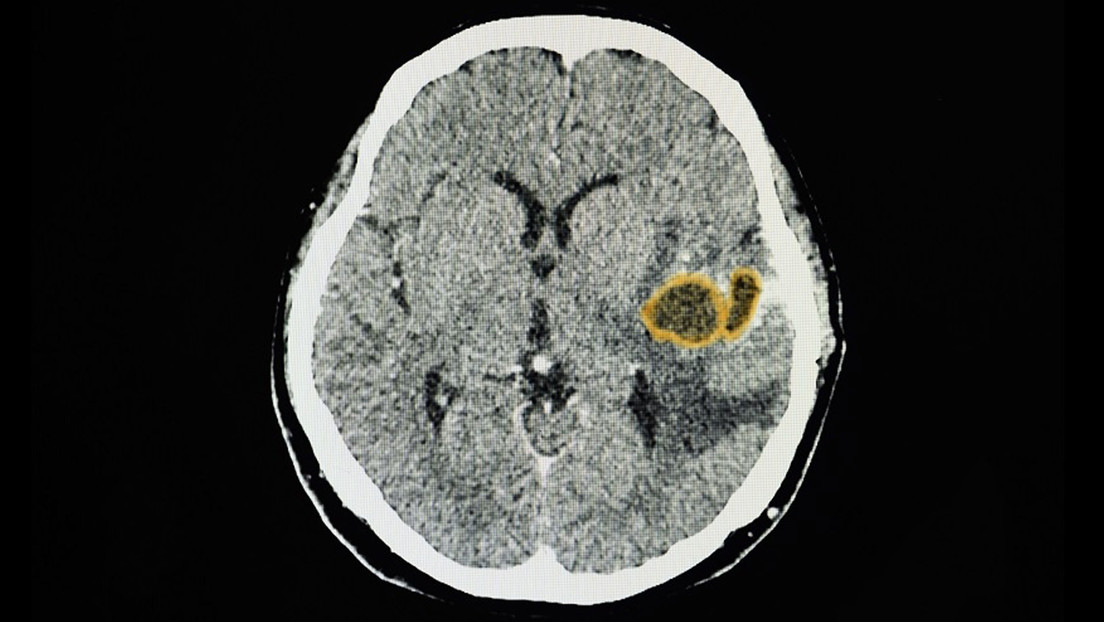

Un absceso cerebral es una acumulación de pus y material infectado en el tejido del cerebro. Pueden causar convulsiones, trastornos visuales o cambios en la visión, el habla, la coordinación o el equilibrio. Su tratamiento a menudo incluye procedimientos quirúrgicos.